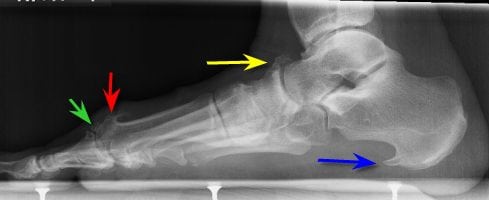

Шипы пяточных костей

Остеофиты на пятке (по МБК 10 болезнь имеет номер M25) развиваются вследствие нарушения кальциевого обмена либо по причине воспалительных процессов в стопе. Пяточные наросты диагностируются у 50 % людей с тяжелыми заболеваниями позвоночника или суставов.

Симптомы и лечение остеофитов на пятке определяются степенью запущенности патологии и ее первопричиной. Терапия для таких пациентов — только комплексная.

Если остеофиты не мешают человеку ходить, не вызывают сильной боли, для облегчения состояния можно лечиться народными средствами.

При крупных остеофитах, поражающих пяточную кость и мягкие ткани, показано хирургическое лечение (можно практиковать в Израиле и других странах). Однако хирургическое лечение очень болезненное и не всегда может полностью избавить от патологии.

Изменения в стопе

Остеофиты стопы локализуются на пяточной кости. Провоцирует данное состояние пяточная шпора. Реже такие образования размещаются в области пальцев. Симптомы остеофитов голеностопном суставе: деформация, боль во время ходьбы.

Помимо терапии остеоартроза стопы таблетками, удаления остеофитов лазером и оперативным вмешательством, лечить их можно с помощью специальных фиксаторов и стелек. Часто используется тейпирование (накладывание лент для закрепления связочного аппарата), применение ночных ортезов.